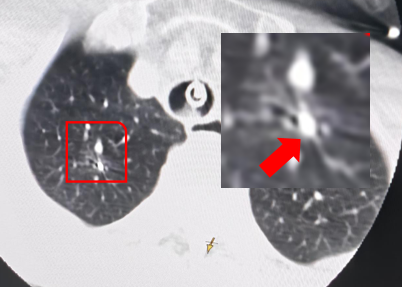

患者陈先生,83 岁,2 年前体检发现双肺多发磨玻璃结节,其中右肺上叶尖段结节在年度随访过程中右肺尖部结节逐渐增大、实变成分逐渐增多。今年 8 月份复查时该结节已经具有空泡征、毛刺征、血管穿行等多个恶性征象,考虑肺癌可能性大,需要积极处理,患者到我院肺结节门诊就医。呼吸内科梁伟权主任综合评估患者全身情况、基础疾病及肺结节位置等情况。

操作精度要求高:结节大小约 16×11 mm,冷冻球囊必须尽可能位于病灶中心部位才能确保消融范围完全覆盖病灶;

与其他影像设备灵活适配:AI 导航机器人辅助下手术团队把导管准确送达目标支气管,借助 DSA 影像系统(CBCT)确认导管精准抵达病灶后,实时反馈冰球形成范围,确保消融操作在多模态影像的全程监控下稳定进行,为精准控制消融范围提供了坚实支撑;

实现稳定消融: 在机器人机械臂及锁止功能与 DSA 系统(CBCT)的双重保障下,实施冷冻消融全过程,导管位置始终精准稳定,冰球形成范围完全可控,最终冰球覆盖病灶边缘超过 0.5 cm,确保肿瘤细胞完全灭活;